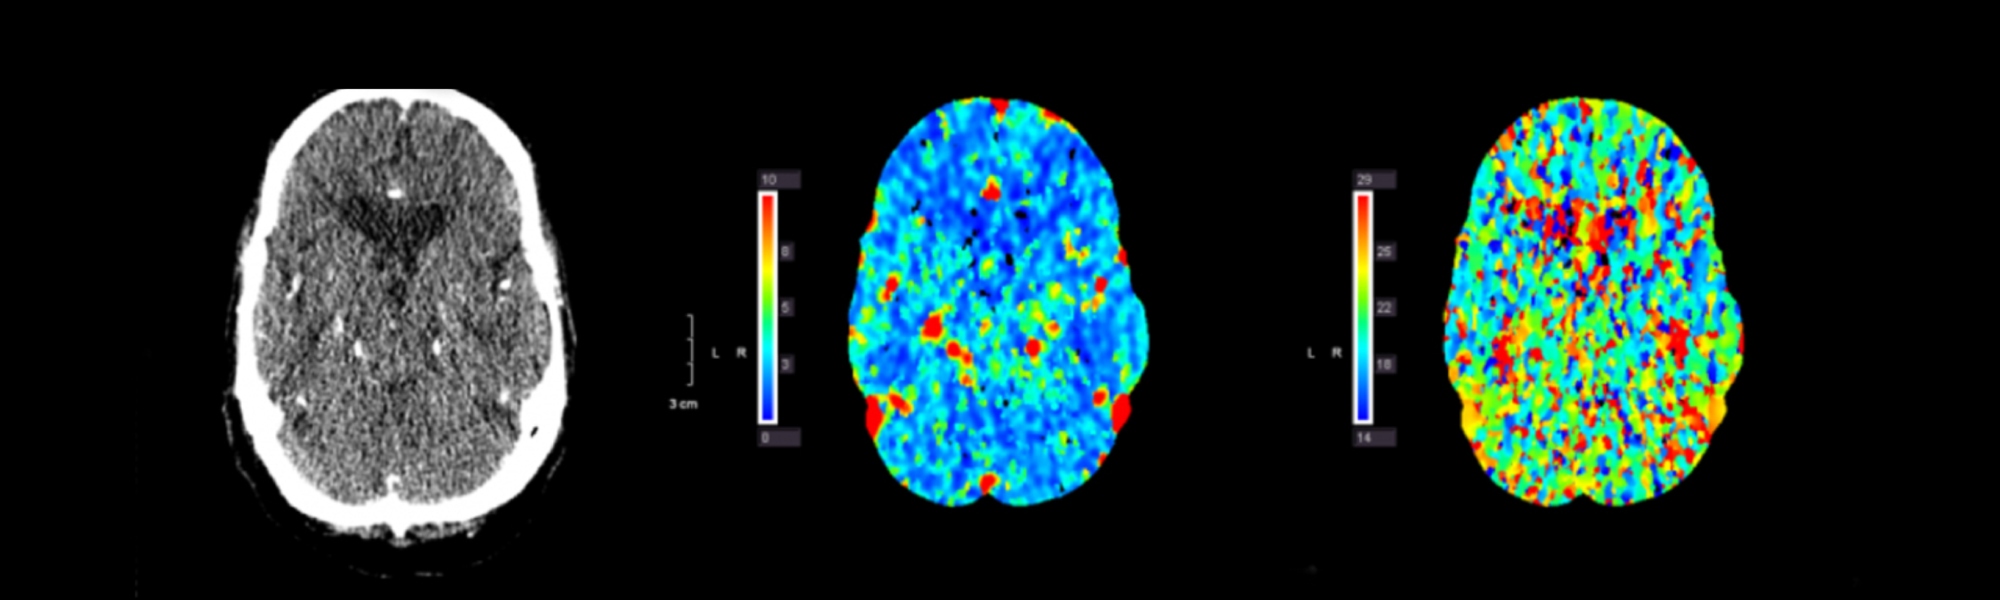

Hemangioblastoma